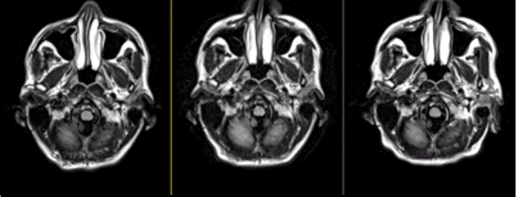

View a Case-Based Learning video on ARIA, presented by neuroradiologist, Dr Jerome Barakos. Through case examples, this on-demand video aims to familiarize you with ARIA and provide you with practical knowledge of how to detect, diagnose and differentiate ARIA from other pathologies in clinical practice.